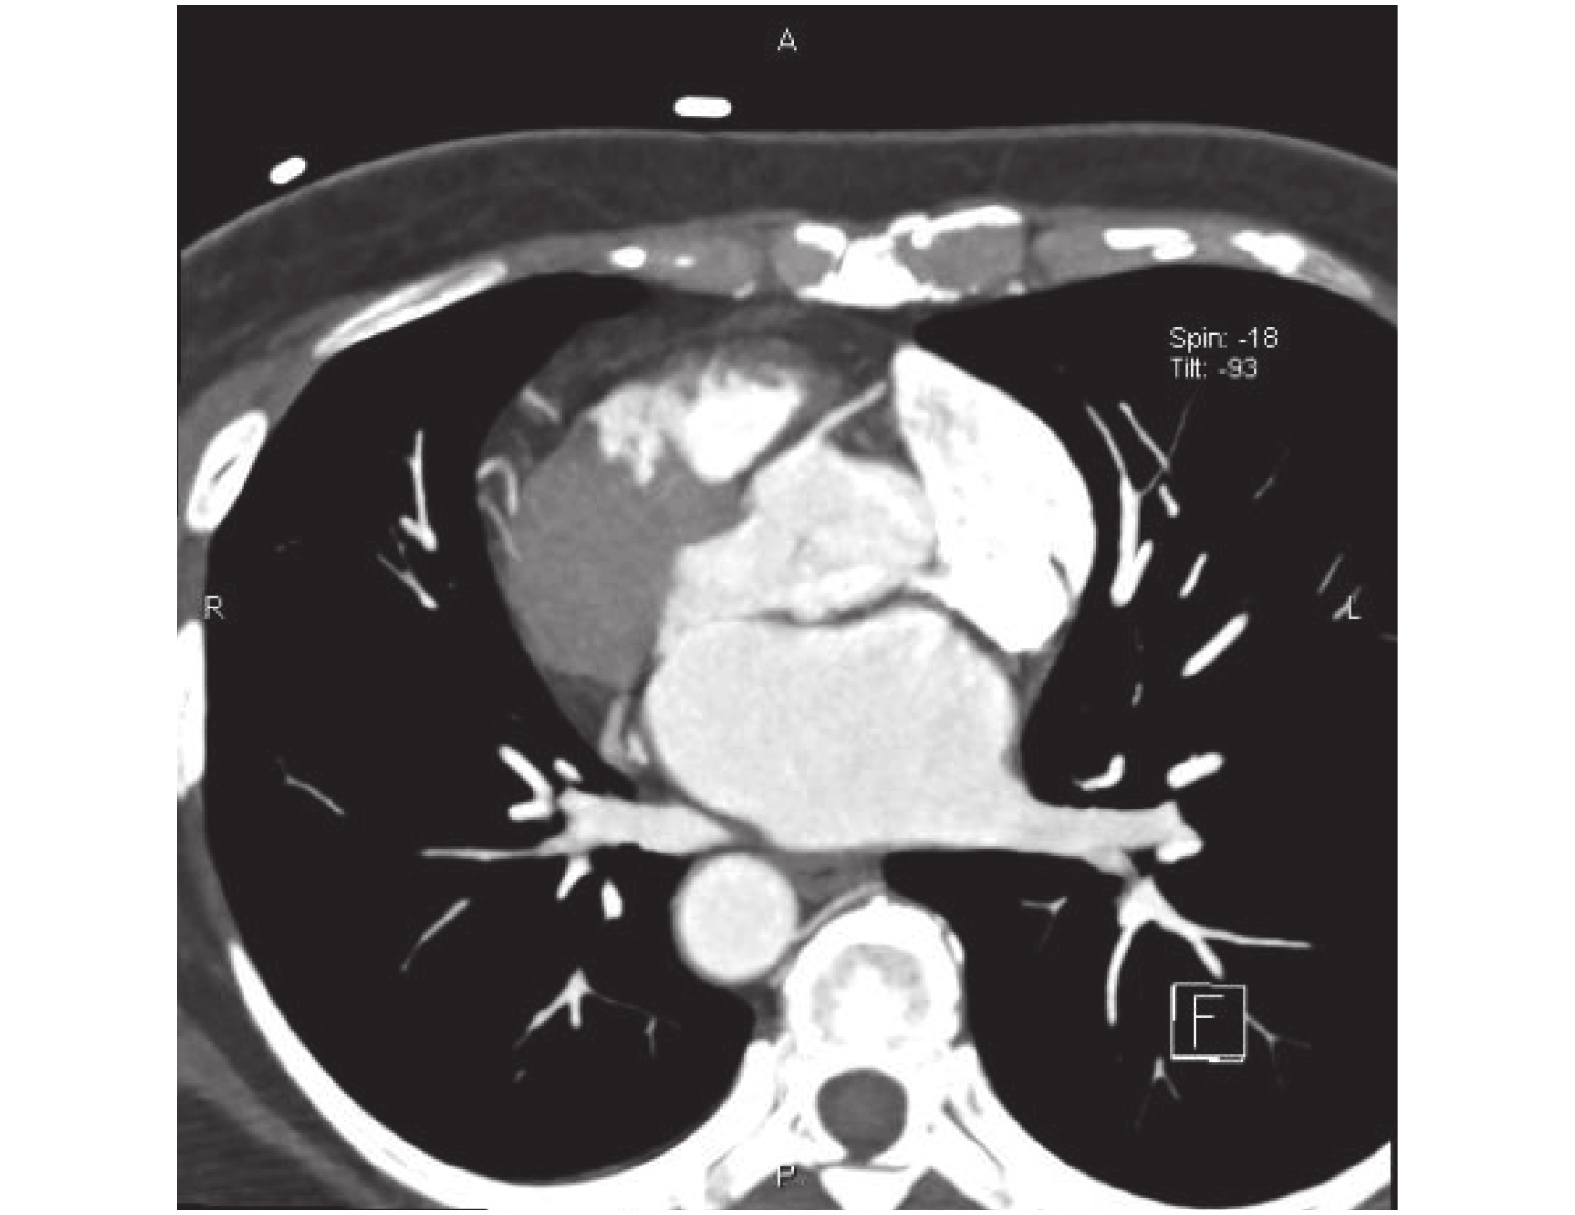

臨床資料 患者,女,57 歲,因“體檢發現左下肺結節 1 個月”入院,無咳嗽咳痰、咯血胸痛、氣急胸悶、低熱盜汗等不適。無高血壓、糖尿病史。胸部 X 線片檢查為鏡面右位心(圖 1)。胸腹部 CT 示:全內臟反位(situs inversus totalis,SIT,(圖 2、圖 3),左肺下葉混合磨玻璃結節(圖 4),大小約 16 mm×12 mm,密度欠均勻,內見空泡影,實性部分 CT 值約 31 Hu,磨玻璃結節部分 CT 值約–435 Hu,形態呈不規則,邊緣稍模糊,邊界基本清楚,鄰近肺野清楚,考慮侵襲性腺癌可能性大。心電圖示:右位心,Ⅰ導聯、aVL 導聯 P 波倒置,QRS 波以向下波為主,aVR 導聯 P 波直立,V1~V5 導聯 R 波逐漸減小,S 波逐漸增深。